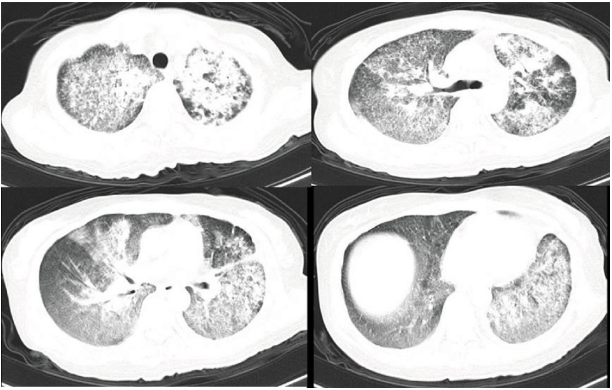

1个月前,患者接受胸部CT扫描,CT显示双肺弥漫分布的微小结节,镜面状毛玻璃密度影及实变影,边缘模糊,胸膜下区相对较少,双肺纵隔和肺门可见多发钙化淋巴结影,双侧胸腔有轻微积液(图1)。

图1. 患者胸部CT改变特点